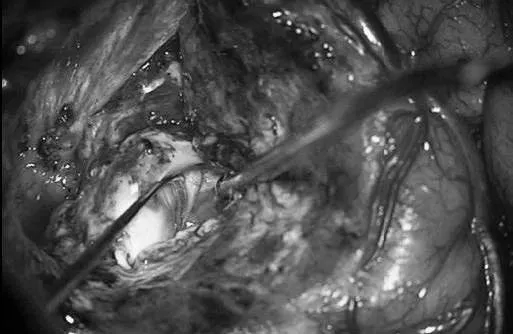

颅内动静脉畸形经动脉(A)与经静脉(B)两种治疗入路的对比示意图。